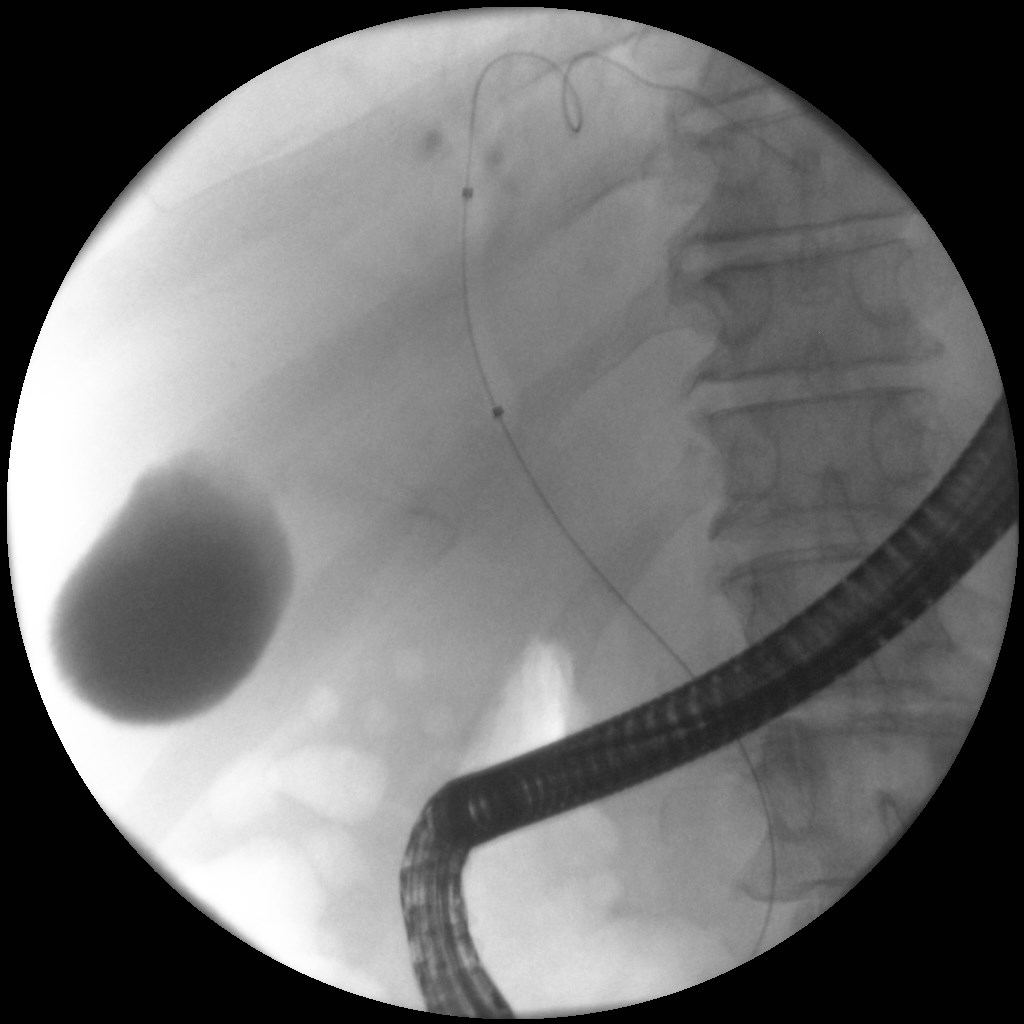

Άνδρας 61 ετών με ανώδυνο αποφρακτικό ίκτερο υποβλήθηκε σε μαγνητική τομογραφία που έδειξε διάταση ενδοηπατικών χοληφόρων με στένωση του κοινού ηπατικού πόρου και της συμβολής του δεξιού και αριστερού ηπατικού πόρου, εικόνα συμβατή με χολαγγειοκαρκίνωμα της πύλης του ήπατος (όγκος Klatskin, Bismuth IV). Επίσης συνυπήρχε θρόμβωση πυλαίας φλέβας, ασκιτικό υγρό και ευμεγέθεις λεμφαδένες πέριξ της κεφαλής του παγκρέατος και στον ηπατοδωδεκαδακτυλικό σύνδεσμο. Το νεόπλασμα κρίθηκε ανεγχείρητο μετά από συζήτηση σε συμβούλιο πολλαπλών ειδικοτήτων και ο ασθενής υποβλήθηκε σε ενδοσκοπική παλίνδρομη χολαγγειο-παγκρεατογραφία (ERCP) για αποσυμφόρηση του ικτέρου. Στην ERCP έγινε λήψη κυττάρων από την περιοχή της στένωσης με βούρτσα κυτταρολογικής, διαστολή της στένωσης με μπαλόνι και επιτυχής τοποθέτηση ακάλυπτου, μεταλλικού stent μήκους 10εκ. Μετά την ERCP, ο ασθενής βελτιώθηκε κλινικά με σημαντική υποχώρηση του ικτέρου.

ERCP

Τοποθέτηση μεταλλικού stent